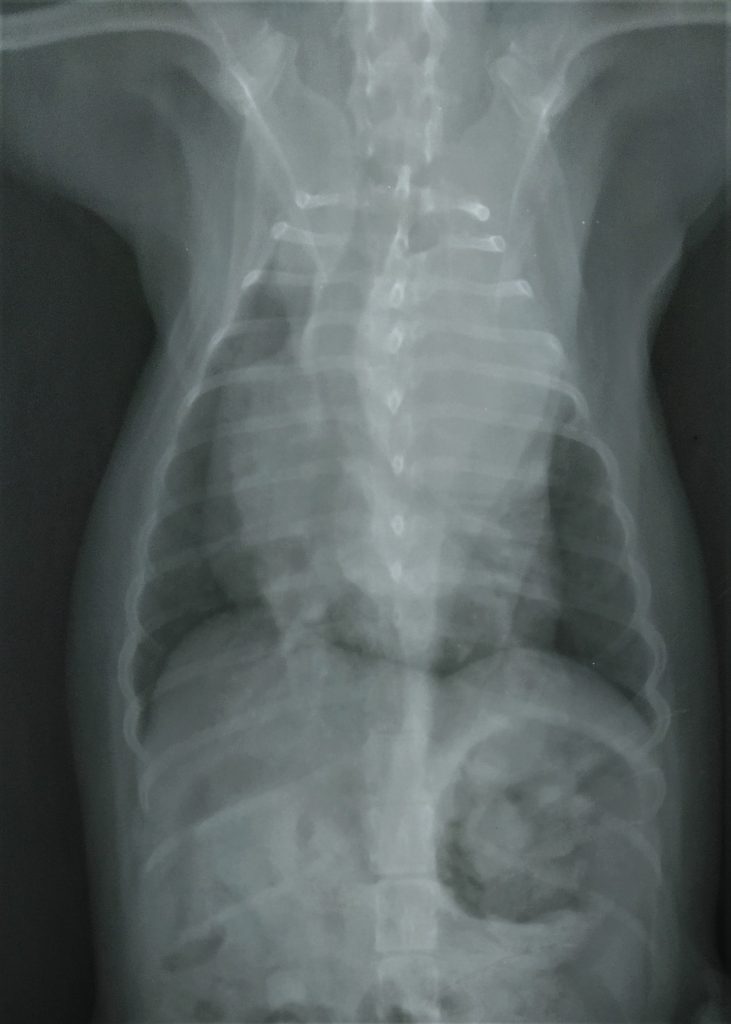

Estudio Radiográfico

Pruebas realizadas por su veterinario y aportadas a DXIA.

Desplazamiento traquea cranealmente, perdiéndose el ángulo normal que debe tener con la columna. Cardiomegalia derecha sobre todo zona aurícula derecha o base cardíaca. Edema perihiliar leve.

Se observa estructura de densidad tejido blando que se superpone en zona de la silueta cardíaca, correspondiente a la zona de la aurícula derecha produciendo efecto silueta. Cardiomegalia. Aerofagia. Pulmón sin patrón alterado.